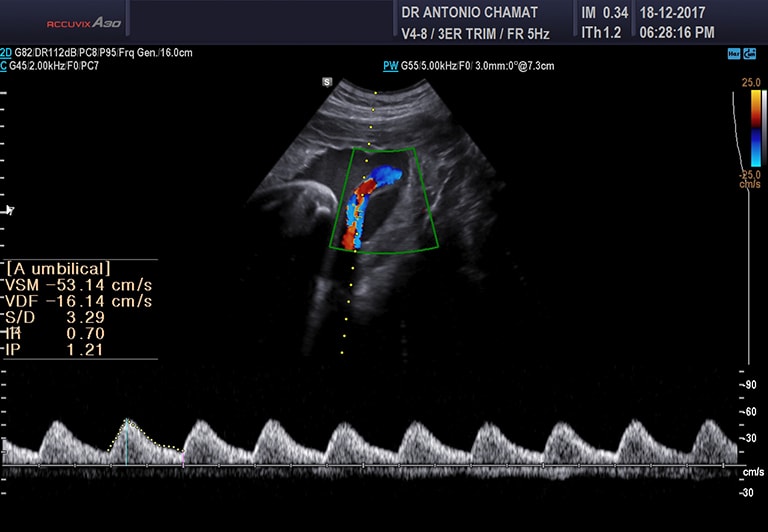

Ecografía Doppler de circulación fetal y placentaria

Consiste en evaluar la circulación sanguínea a nivel del cordón umbilical (que nos dice cómo está funcionando la placenta) y en diferentes vasos sanguíneos fetales. El feto puede experimentar cambios en la circulación sanguínea para compensar y proteger sus órganos principales como cerebro y corazón, esto puede darse en situaciones como restricción del crecimiento fetal, preeclampsia, inmunización por el tipo de sangre (Rh), malformaciones cardiacas y de otro tipo, así como en otras enfermedades fetoplacentarias.

El doppler también es de suma utilidad para evaluar la inserción de la placenta la cual en ocasiones puede estar anormalmente adherida (Acretismo placentario) cuando existe una cicatriz uterina previa como en las embarazadas que ya tienen una cesárea anterior.